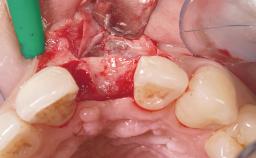

This 43-year-old male patient, a non-smoker, came to our practice because of a fracture of tooth 12 caused by a bicycle accident. Due to the combined para- and infrabony crown and root fracture, tooth extraction, and subsequent implant placement were suggested to the patient as the therapy of choice. The patient had high esthetic expectations with regard to the treatment outcome and asked for an immediate fixed provisional restoration. His individual esthetic risk profile summed up to a medium esthetic risk.

| Placement Protocol | Immediate implant placement |

| Socket Morphology | Single-root socket |

| Socket Integrity | Sufficient, with intact bone walls |